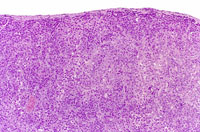

A cholangiocarcinoma with a prominent scirrhous reaction